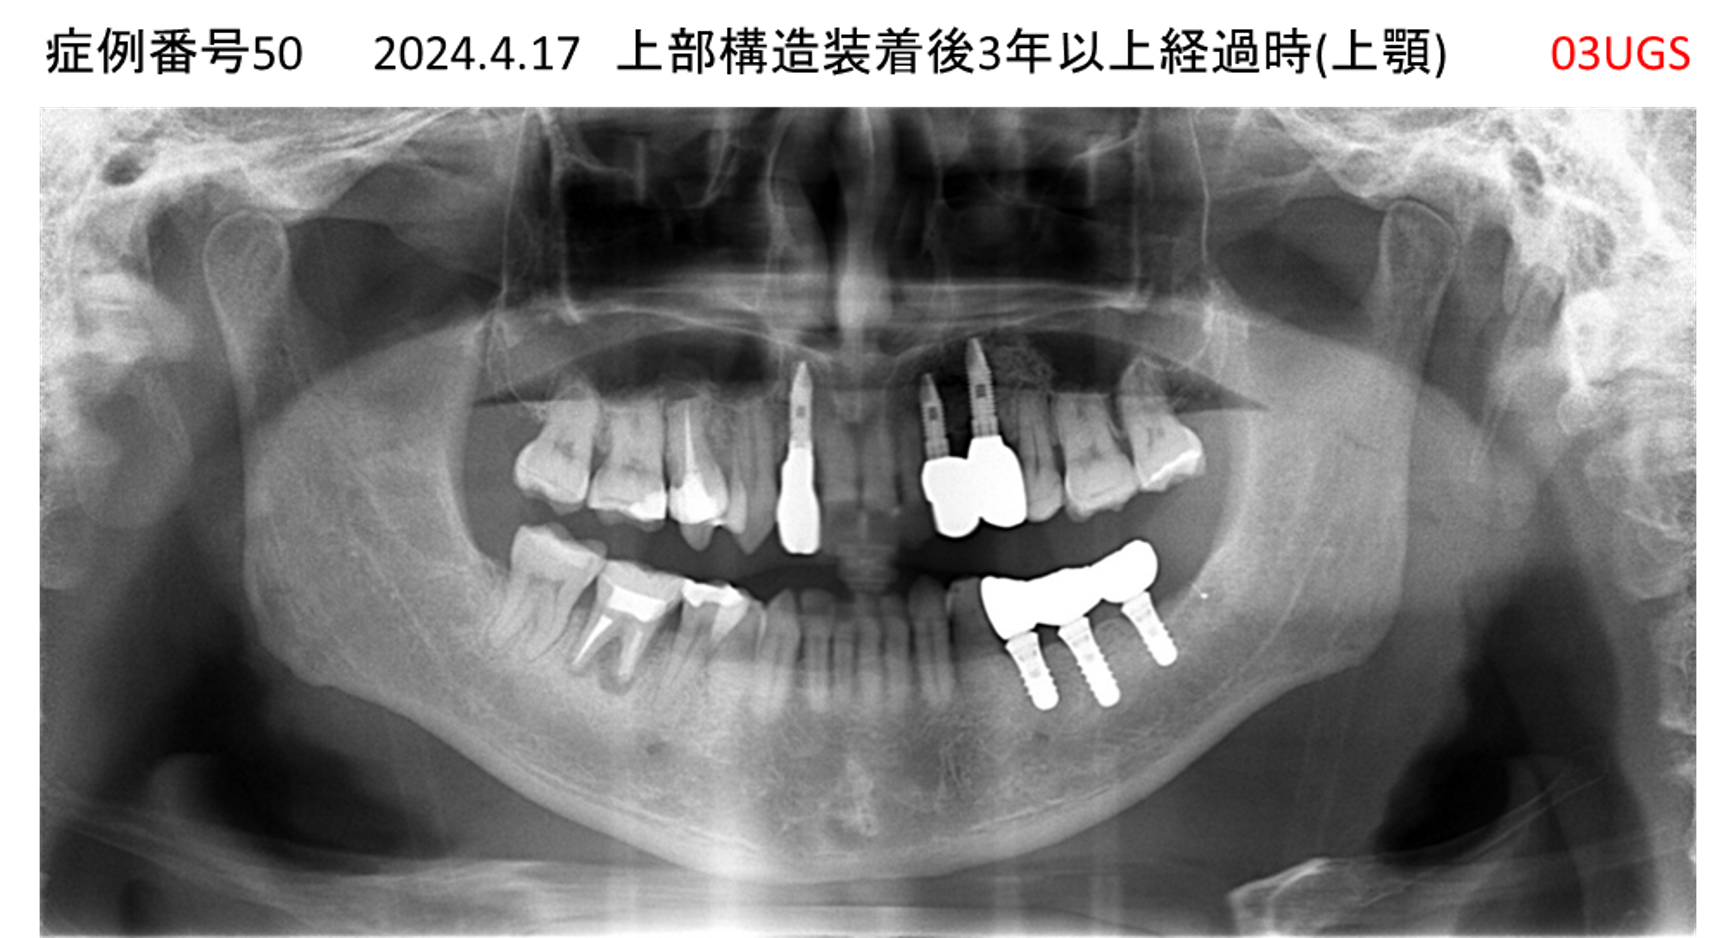

奥歯で噛めない患者様のインプラント症例

| 治療名称 |

インプラント |

| 治療費用 |

365万円+税 |

| 治療期間 |

5か月 |

| 患者さんの症状(主訴) |

奥歯で噛めない。上の前歯が揺れてきた。 |

| 治療内容 |

抜歯即時インプラント |

| 治療結果 |

食事に困らない。見た目がとても良くなった。 |

| 治療の注意点(リスク/副作用) |

インプラントが壊れたら再治療が必要 |